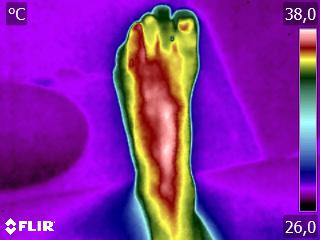

Como no caso da sequência de termogramas abaixo de uma paciente do sexo feminino, 51 anos e sem comorbidades e que sofreu um trauma de pé esquerdo durante a prática esportiva. Fez exame de Raio-X e não foi detectado fraturas, mas ainda apresentava muita dor. No 4º dia de pós trauma realizou uma Análise Termofuncional e foi detectado alterações térmicas condizente com processo inflamatório.

A terapia então foi ajustada para tratar esta lesão, não sobrecarregando a mesma e não apenas tratando a sintomatologia, mas sim até sua completa restauração.

Como no caso apresentado acima, a Termofuncional lhe proporciona não só “enxergar” as alterações térmicas, mas também uma maior segurança na terapia, com isso você poderá ter resultados muito mais eficazes. Além de lhe garantir segurança jurídica para cada procedimento que você realizar na sua reabilitação.